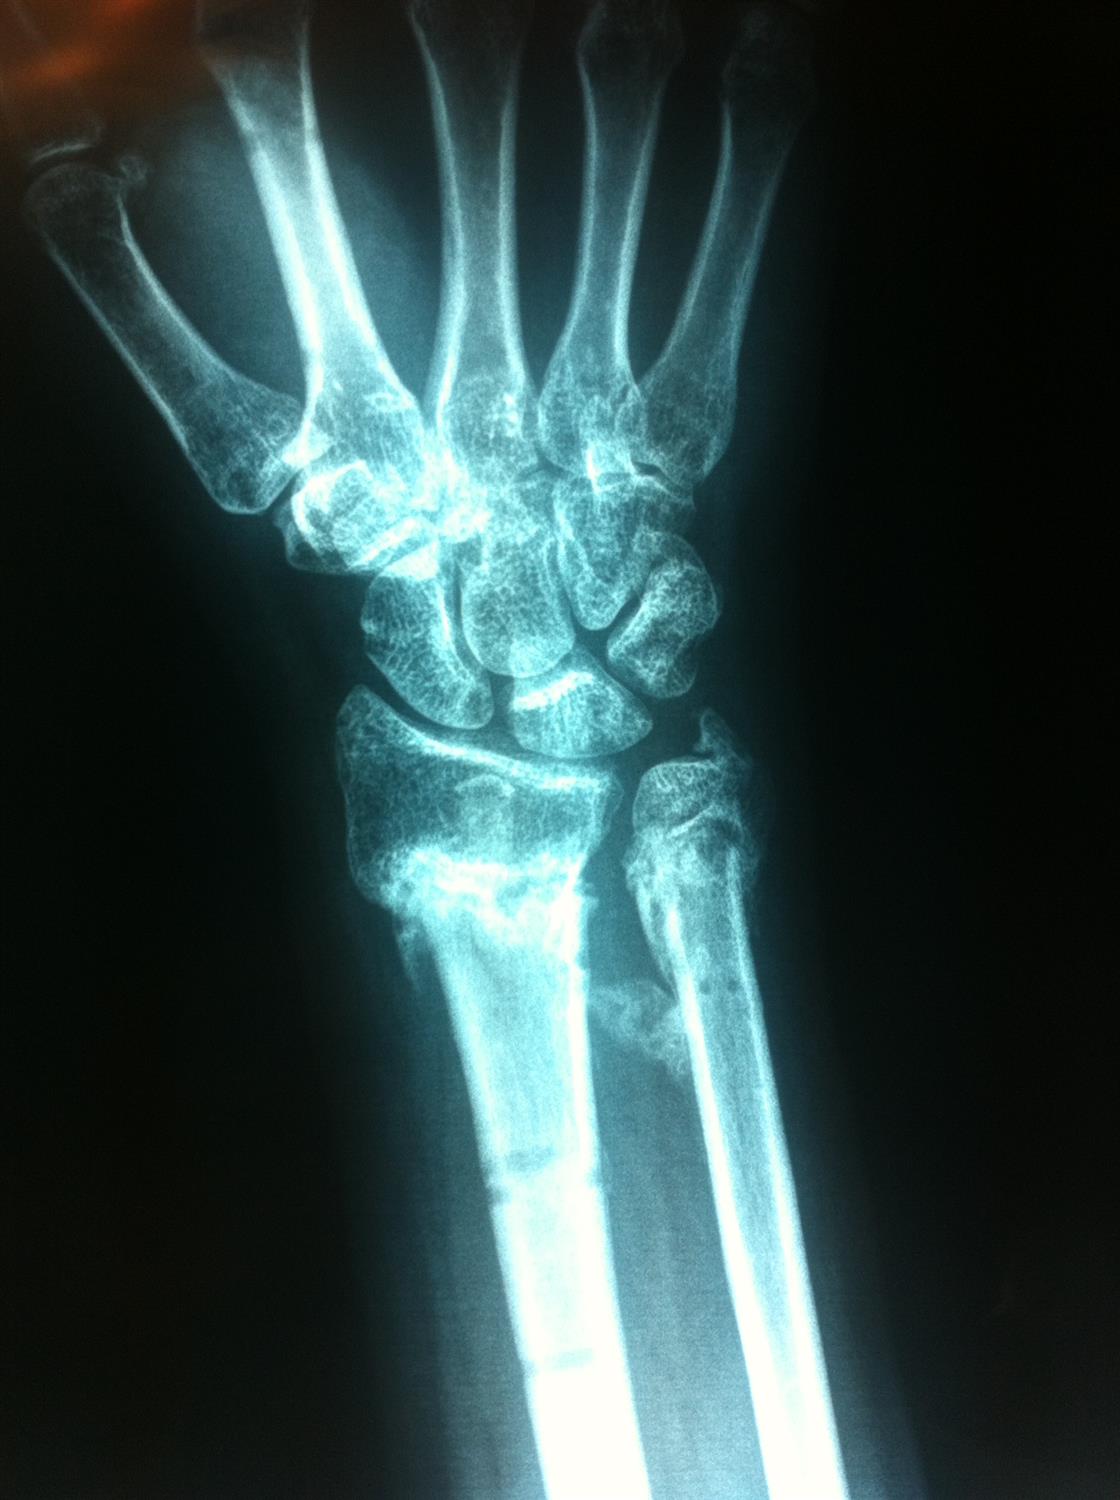

Distal Radius Ulna Fracture Orthobullets . Radial head fracture with an interosseous membrane injury extending to druj unstable relationship between ulna and radius leads to proximal migration of the radius Distal radius fractures are the most common site of pediatric forearm fractures and generally occur as a result of a fall on an outstretched hand with the wrist extended. Ulnar styloid fracture occurs together with distal radius fracture that has high degree of initial displacement associated with. Distal radius fractures are the most common orthopaedic injury and generally result from fall on an outstretched hand. The american academy of orthopaedic surgeons and the american society for surgery of the hand released updated clinical practice guidelines in. Distal radius fracture is usually associated with ulnar styloid fracture. Whether to fix the ulnar styloid or not remains a surgical dilemma as. Radius and ulnar shaft fractures, also known as adult both bone forearm fractures, are common fractures of the forearm caused by.

Radius and ulnar shaft fractures, also known as adult both bone forearm fractures, are common fractures of the forearm caused by. Whether to fix the ulnar styloid or not remains a surgical dilemma as. Distal radius fracture is usually associated with ulnar styloid fracture. Radial head fracture with an interosseous membrane injury extending to druj unstable relationship between ulna and radius leads to proximal migration of the radius Ulnar styloid fracture occurs together with distal radius fracture that has high degree of initial displacement associated with. Distal radius fractures are the most common site of pediatric forearm fractures and generally occur as a result of a fall on an outstretched hand with the wrist extended. Distal radius fractures are the most common orthopaedic injury and generally result from fall on an outstretched hand. The american academy of orthopaedic surgeons and the american society for surgery of the hand released updated clinical practice guidelines in.

Distal Radius Ulna Fracture Orthobullets Ulnar styloid fracture occurs together with distal radius fracture that has high degree of initial displacement associated with. Radius and ulnar shaft fractures, also known as adult both bone forearm fractures, are common fractures of the forearm caused by. Distal radius fractures are the most common site of pediatric forearm fractures and generally occur as a result of a fall on an outstretched hand with the wrist extended. Distal radius fractures are the most common orthopaedic injury and generally result from fall on an outstretched hand. Ulnar styloid fracture occurs together with distal radius fracture that has high degree of initial displacement associated with. The american academy of orthopaedic surgeons and the american society for surgery of the hand released updated clinical practice guidelines in. Distal radius fracture is usually associated with ulnar styloid fracture. Radial head fracture with an interosseous membrane injury extending to druj unstable relationship between ulna and radius leads to proximal migration of the radius Whether to fix the ulnar styloid or not remains a surgical dilemma as.